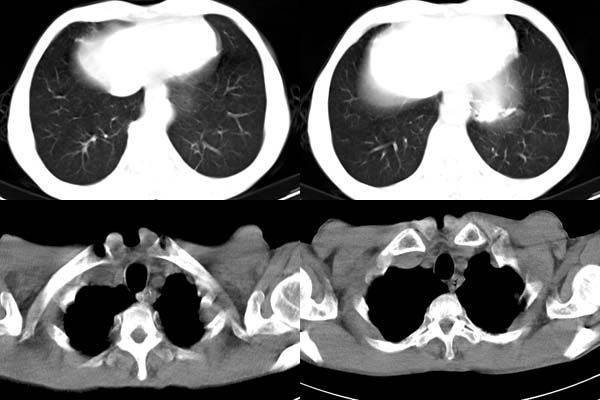

患者,男,65岁,咳嗽,胸痛

胸膜下见多个软组织结节且以宽基底与胸膜相连,上部肋骨似见骨质破坏,考虑:恶性胸膜间皮瘤。

ct所见;左下肺可见片状阴影,密度不均,边缘尚清晰,胸膜方向见有条索相连,纵隔窗未见具体结节。左侧胸膜下见多个软组织结节且以宽基底与胸膜相连,右侧胸锁关节层面亦见软组织结节广基与胸膜相连。纵隔未见肿大淋巴结,气管,支气管开口正常。

左肺下叶基底段见结节样稍高密度影,内密度不均匀,边缘不清,可见索条影与邻近胸膜粘连,左侧胸膜上见多个结节影,以宽基底与胸膜粘连.纵隔不宽,内未见明确肿大的淋巴结.

考虑:周围型肺ca伴左侧胸膜转移可能性大 ,不完全除外左肺下叶炎性假瘤,左侧胸膜间皮瘤可能,建议强化ct扫描。

ct所见:左肺上、下叶近胸膜肺外带可见多个大小不等的结节灶,边界清楚,边缘比较光整。近胸膜病灶似与胸膜以宽基底紧连。提供的病史比较简单,我考虑:1、胸膜原发肿瘤可能性大(就形态来看恶性可能性不大);那么大胆的设想一下,左下叶结节是否与它有必然的联系呢?也可以是结核或周围型肺癌。2、还可以考虑为胸膜和肺内的都是转移灶,病人65岁,是不是其他部位的恶性肿瘤转移过来的呢?因为病灶比较表浅,但一侧发病较少见。3、周围型肺癌并胸膜转移的可能性比较小,一是肺内病灶较小,单发,胸膜结节相对较多,位置较远,临近胸膜无受侵。